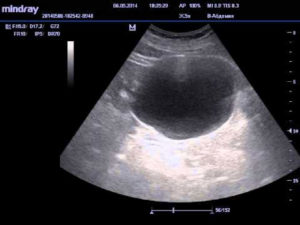

Патологические состояния на УЗИ аппарате выглядят утолщением стенок, которые превышают допустимые 5 мм. Это явления возникает при закрытом пространстве камнем или опухолью, паразитарных инвазиях, туберкулезе. Данное явление обычно сопровождает повышение допустимого объема остаточной мочи.

Равномерное или очаговое утолщение стенок, при котором размеры превышают 5 мм., характеро для таких заболеваний как:

- закрытие просвета органа (опухоль, камень);

- паразитарные инвазии (например, поражение шистосомами);

- туберкулез мочевыводящих путей (появление на стенках туберкулезных гранулем).

- Утолщения стенок. Стенку можно считать толстой при превышении ею толщины 4-5 миллиметров. При этом существует выделение равномерного или локального типа утолщения. Выявление этого симптома в большинстве случаев свидетельствует о наличии хронического цистита. Такое отклонение может привести к дивертикуле мочевого пузыря, его паразитарному поражению, туберкулезному поражению и прочим заболеваниям.

- Эхогенных образований. Представляет собой один из наиболее распространенных симптомов, наблюдаемых в результате УЗИ. Образования могут иметь как опухолевую, так и неопухолевую природу. Могут иметь как подвижный характер, так и примыкать к стенке органа. Вид образования на УЗИ определяется по их эхогенности, например, максимальной эхогенностью обладает камень, минимальной – киста.

Рассмотрим распространенные диагнозы, выявляемые на Узи мочевого пузыря.

Утолщение стенок органа по всей площади у мужчин чаще всего происходит из-за закупорки на уровне простаты. При таких изменениях требуется обследование почек и мочевыводящих путей, исключение гидронефроза.

В случае повышенной плотности стенок органа также необходимо удостоверится в отсутствии дивертикул (выступающих наружу образований). Визуализировать их можно в том случае, если размер дивертикула превышает 1 см в диаметре.

Такие образования эхогенны и проводят ультразвук.

Уплотнение стенок также может быть вызвано острым или хроническим воспалением пузыря или паразитозом. Шистосомы легко визуализируются в следствии повышенной эхогенности структур и наличия кальцинированных включений.